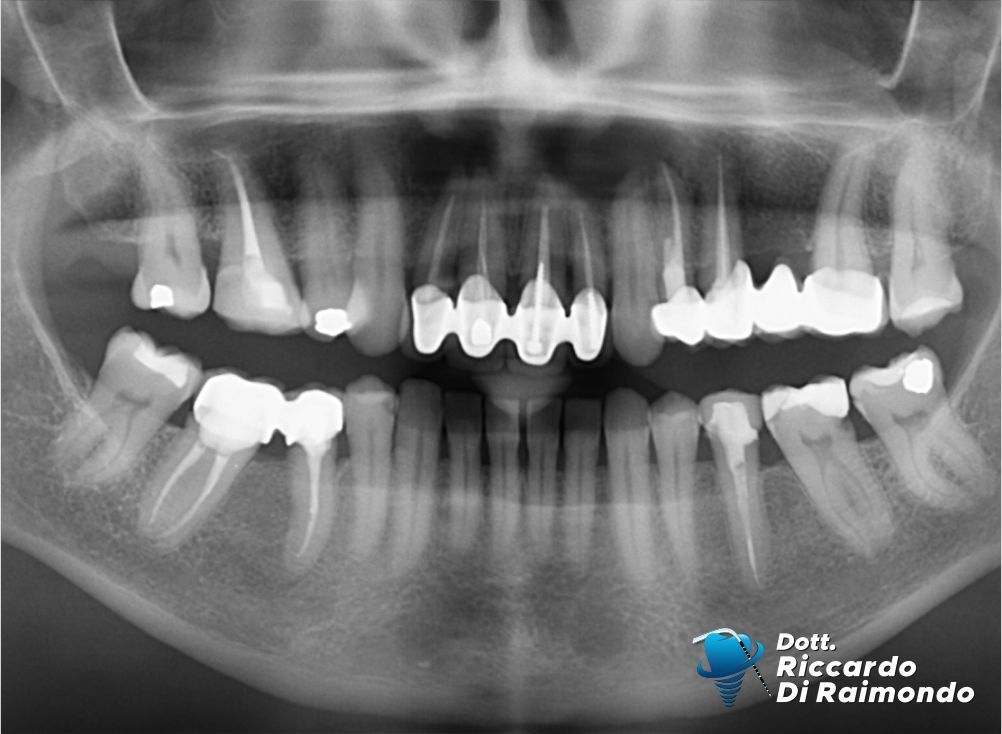

Rimozione cisti mascellare superiore frontale

Dopo il trattamento